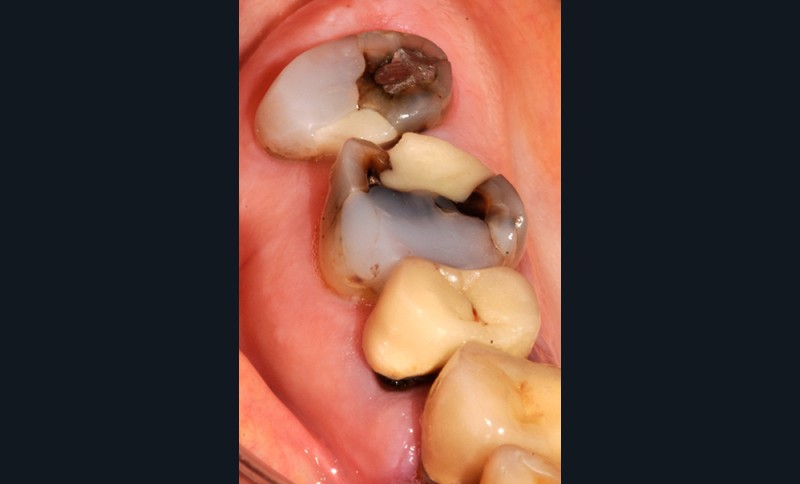

Aspect clinique et radiographique des lésions d’abrasion

Cliniquement, les lésions d’abrasion sont caractérisées par des facettes lisses, une absence de convexité et des bords à angles vifs. La flexibilité du ligament alvéolo-dentaire va entrainer un frottement au niveau des points de contact, qui peuvent se transformer en surfaces de contact (fig. 2c-d, 3 et 4b-c).

Radiographiquement, on observe une perte des cuspides et un aspect plan des faces occlusales (fig. 2a-b et 4a).